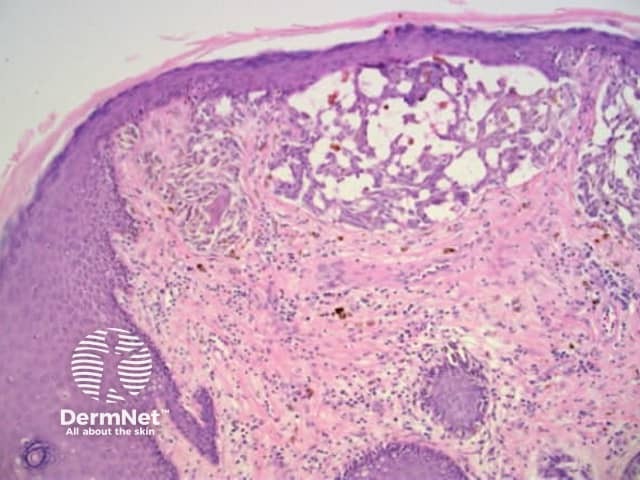

Clods are solid rounded structures of sufficient size to show an appreciable variability in size. Their colour depends on the nature and, in the case of melanin, depth of the substance they comprise (Figures 37-50). Other terms have been used for clods in specific settings such as blue-grey ovoid nests for grey and / or blue clods seen in basal cell carcinoma.

Figure 48. Diagram. Brown, grey and blue clods are due to nests of melanin-containing cells at different levels in the skin. From Kittler et al (1).

Figure 49a Figure 49b Figure 49c Figure 49d

Figure 50a Figure 50b